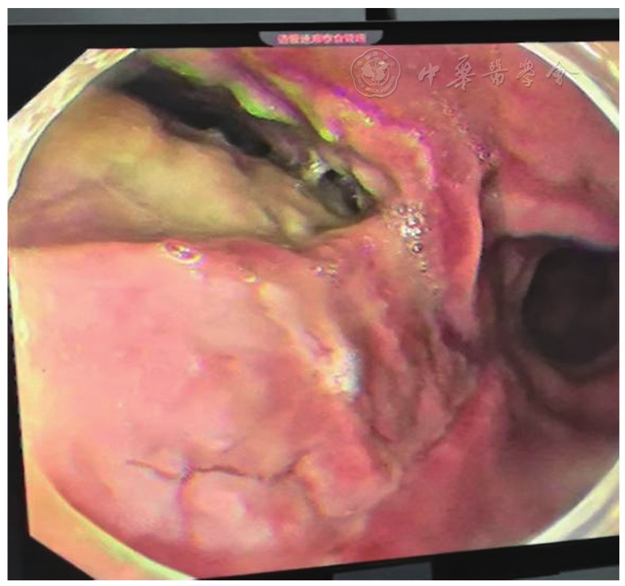

图3 入院第5天完善胃镜检查,食管瘘口长约5 cm,瘘口处可见肿胀并可见胸腔内脓壁